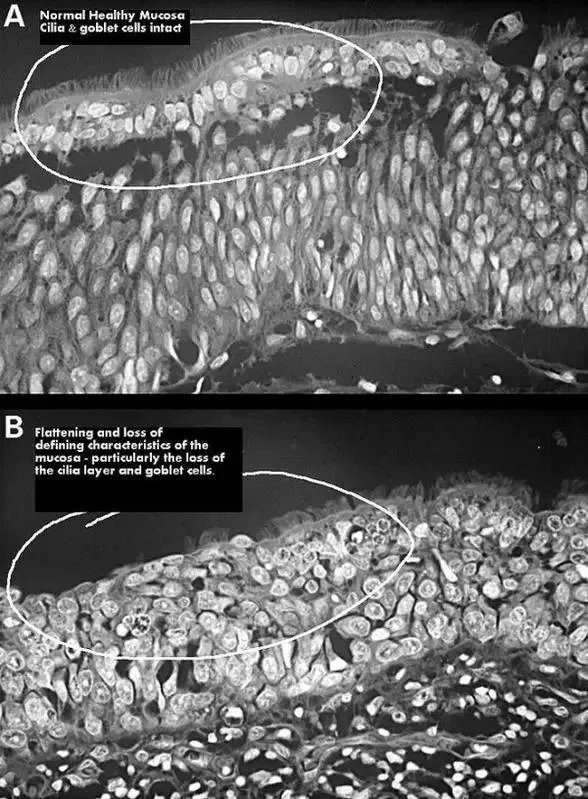

上:正常鼻腔黏膜;下:鼻腔黏膜萎缩,图自wikipedia.org1994年,有学者第一次用空鼻症(又称空鼻综合征Empty Nose Syndrome,ENS)描述这类疾病。从这里我们可以看出,空鼻症和手术的关系,十分密切。真假空鼻症还有些空鼻症患者,虽然也出现了空鼻症的典型症状,但是在检查中,找不到明显的病理改变——下鼻甲完整、黏膜表面光滑、鼻中隔没有偏曲,CT等也未见异常。对此有学者认为,空鼻症的概念并不够准确,应该对其进行更详细的区分。将有病理实据的,称之为空鼻症;将没有病理改变的,称之为类空鼻综合征。类空鼻综合征和手术关系不大,主要跟患者的精神状态有关。抑郁、焦虑等精神性疾病,都有可能出现躯体性症状,如头痛、鼻塞、嗅觉减退等。如果患者恰好接触过相关报道,却没有对空鼻症的全面认识,就有可能“自我诊断”,觉得自己得了空鼻症,反复要求医生进行治疗,甚至和医生产生矛盾。治疗和应对空鼻症的诊断,主要依靠病史和病理检查。患者有没有进行过鼻腔手术?有的话,鼻内镜、CT、MRI检查有没有异常,如鼻甲萎缩、鼻骨萎缩,鼻黏膜干燥、坏死,分泌物异常等?倘若鼻内存在这些病理改变,又具备空鼻症的典型症状,便可以确诊。在治疗方面,既可以用物理手段,提高空气湿度,改善鼻腔的干燥,也可以用药物冲洗鼻腔,清洁鼻腔、改善炎症、保持鼻腔湿润感,还可以通过手术,进行鼻甲重建,恢复鼻粘膜的结构和功能。总的来说,空鼻症是一种十分年轻的疾病,对于其病因、机制都还有很多争议。这里也提醒广大读者,既要对医生有着充分的信任,出现生理或心理异常后及时寻求帮助,又要意识到医生的局限性。毕竟,医学进步是需要时间的。参考文献 李娜, 彭云鹏, 支国成等.以空鼻综合征为例分析医患冲突产生的原因及对策[J].中国医学伦理学, 2015, 28(2): 206–207. 董频, 黄若飞. 鼻腔疾病与精神异常的联系-“空鼻症” 与 “类空鼻综合征”[J].中国医学文摘: 耳鼻咽喉科学, 2014(1): 19–21. 赵宇. “空鼻症” 的认识和思考[J].中国医学文摘: 耳鼻咽喉科学, 2014(4): 227–228. 颜永毅. 鼻腔鼻窦术后的精神异常 (附 3 例报告)[J].中国医学文摘: 耳鼻咽喉科学, 2014(2): 97–98. KUAN E C, SUH J D, WANG M B.Empty nose syndrome[J].Current allergy and asthma reports, 2015, 15(1): 1–5.题图来源:图虫创意

下鼻甲切除术,图自wiki.com通常来说,移除这部分黏膜并不会造成不良后果。不过,意外总是存在。有的患者在术后,因为黏膜缺损,失去了湿润、清洁空气的能力,鼻腔产生严重干燥感;时间长了,鼻腔内部会发生一系列的病理变化,如静脉炎症、血管萎缩等,这些病理改变,又进一步加重黏膜萎缩,引起黏膜不可逆性损伤,上皮鳞状化生,甚至神经细胞纤维变性等。